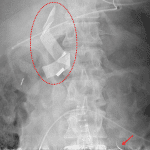

Indication: OR search film

Findings

- Ribbon-like radiopaque body overlying the right upper abdomen

- Incompletely imaged curvilinear radiopaque body overlying the left lower abdomen

- NG tube coils in the gastric fundus with tip overlying the duodenal bulb

- Endotracheal tube with tip approximately 5 cm above the carina

- Central venous catheter tip overlies the superior cavoatrial junction

- Incompletely imaged lower abdominal surgical drain

- Surgical clips in the right hemiabdomen

- Lower abdominal midline surgical staples. An additional staple overlies the left hemiabdomen

- Dense left basilar pulmonary opacity, likely atelectasis

Diagnosis

- Retained surgical foreign bodies

Findings concerning for retained surgical sponge in the right upper quadrant and retained needle in the left lower quadrant. Recommend repeat radiographs after removal.